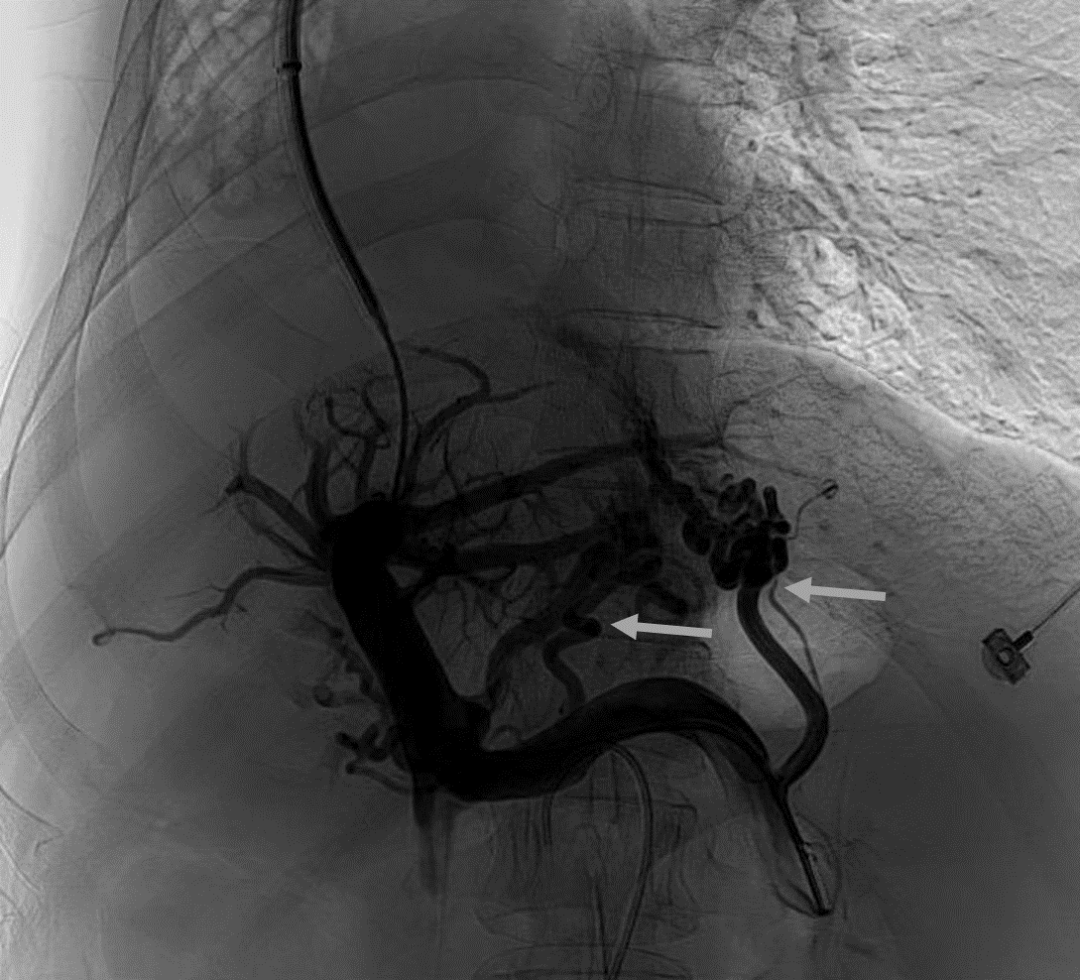

韓國(guó)宏教授介紹,TIPS手術(shù)是通過在肝靜脈與門靜脈之間的肝實(shí)質(zhì)內(nèi)建立分流通道,通過降低門靜脈壓力來預(yù)防和治療因門靜脈高壓引起的食管胃底曲張靜脈破裂出血或頑固性腹水。該手術(shù)不用開刀、創(chuàng)傷小、操作過程復(fù)雜、技術(shù)難度大、安全風(fēng)險(xiǎn)高,是目前外周血管介入中難度最大的手術(shù)之一。再加上人群中右位心發(fā)病率極低(約萬分之一),經(jīng)查閱文獻(xiàn),在國(guó)內(nèi)外尚未有類似病例報(bào)道,無經(jīng)驗(yàn)參考。在右位心基礎(chǔ)上行TIPS術(shù),無疑是難上加難。我們反復(fù)研究患者肝臟及心血管的特殊情況,詳細(xì)討論了手術(shù)方案,決定放棄常規(guī)的肝靜脈穿刺,另辟蹊徑,選擇高難度高風(fēng)險(xiǎn)的肝后段下腔靜脈穿刺門靜脈左支,憑借多年的經(jīng)驗(yàn)和嫻熟的技術(shù)最終成功的在下腔靜脈與門靜脈之間放置了TIPS專用支架,術(shù)后門靜脈壓力梯度從術(shù)前的19mmHg降至3mmHg,曲張靜脈消失,解決了困擾曹女士多年上消化道出血的困擾?;颊咝g(shù)后第二天即可正常下床活動(dòng)。